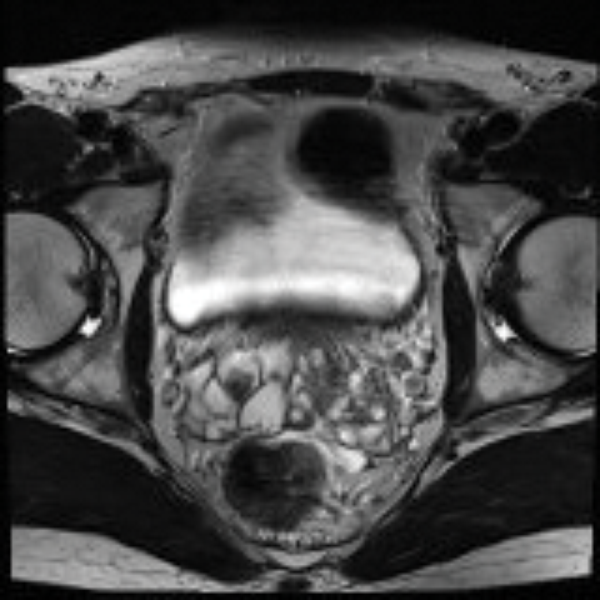

Figure 1: MRI image showing calculi in bilateral seminal vesicle.

Transrectal ultrasound (TRUS) is a safe non-invasive technique and is performed initially to view the prostate and seminal vesicles and can also diagnose seminal vesicle dilatation, calculi and seminal vesiculitis [1,6]. However, MRI (Figure 1) offers a 3D view of the seminal vesicles and allows surgical planning [6,10].